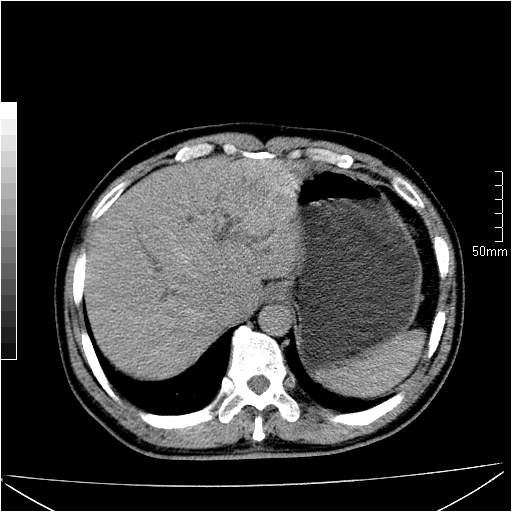

男性,54岁,皮肤黄染,搔痒一周余.b超示肝左叶回声异常.初步诊断1胆总管下段结石2胆囊结石伴慢性胆囊炎请各位战友帮忙看一下肝脏多发低密度如何解释恰当.增强效果不是很好.请大家见谅.

胆总管及肝内胆管扩张,考虑是结石!但,肝内的低密度区增强不明,可能是肝ca,因为肝ca在增强时呈快进快出.另年胆总管扩张原因,可以考虑一下是不是,胆管ca.再次要考虑肝内的低密度是否为海绵状血管瘤所致!

首先,胆总管下端结石梗阻伴肝内胆管扩张可确定。

其次,增强动脉期肝静脉显影,肝实质密度不均。——此为右心功能不全引起肝淤血的表现。

另外,肝八段低密度占位,呈多灶性,考虑肝脓肿或肝癌可能,(图像质量欠佳)建议进一步检查。